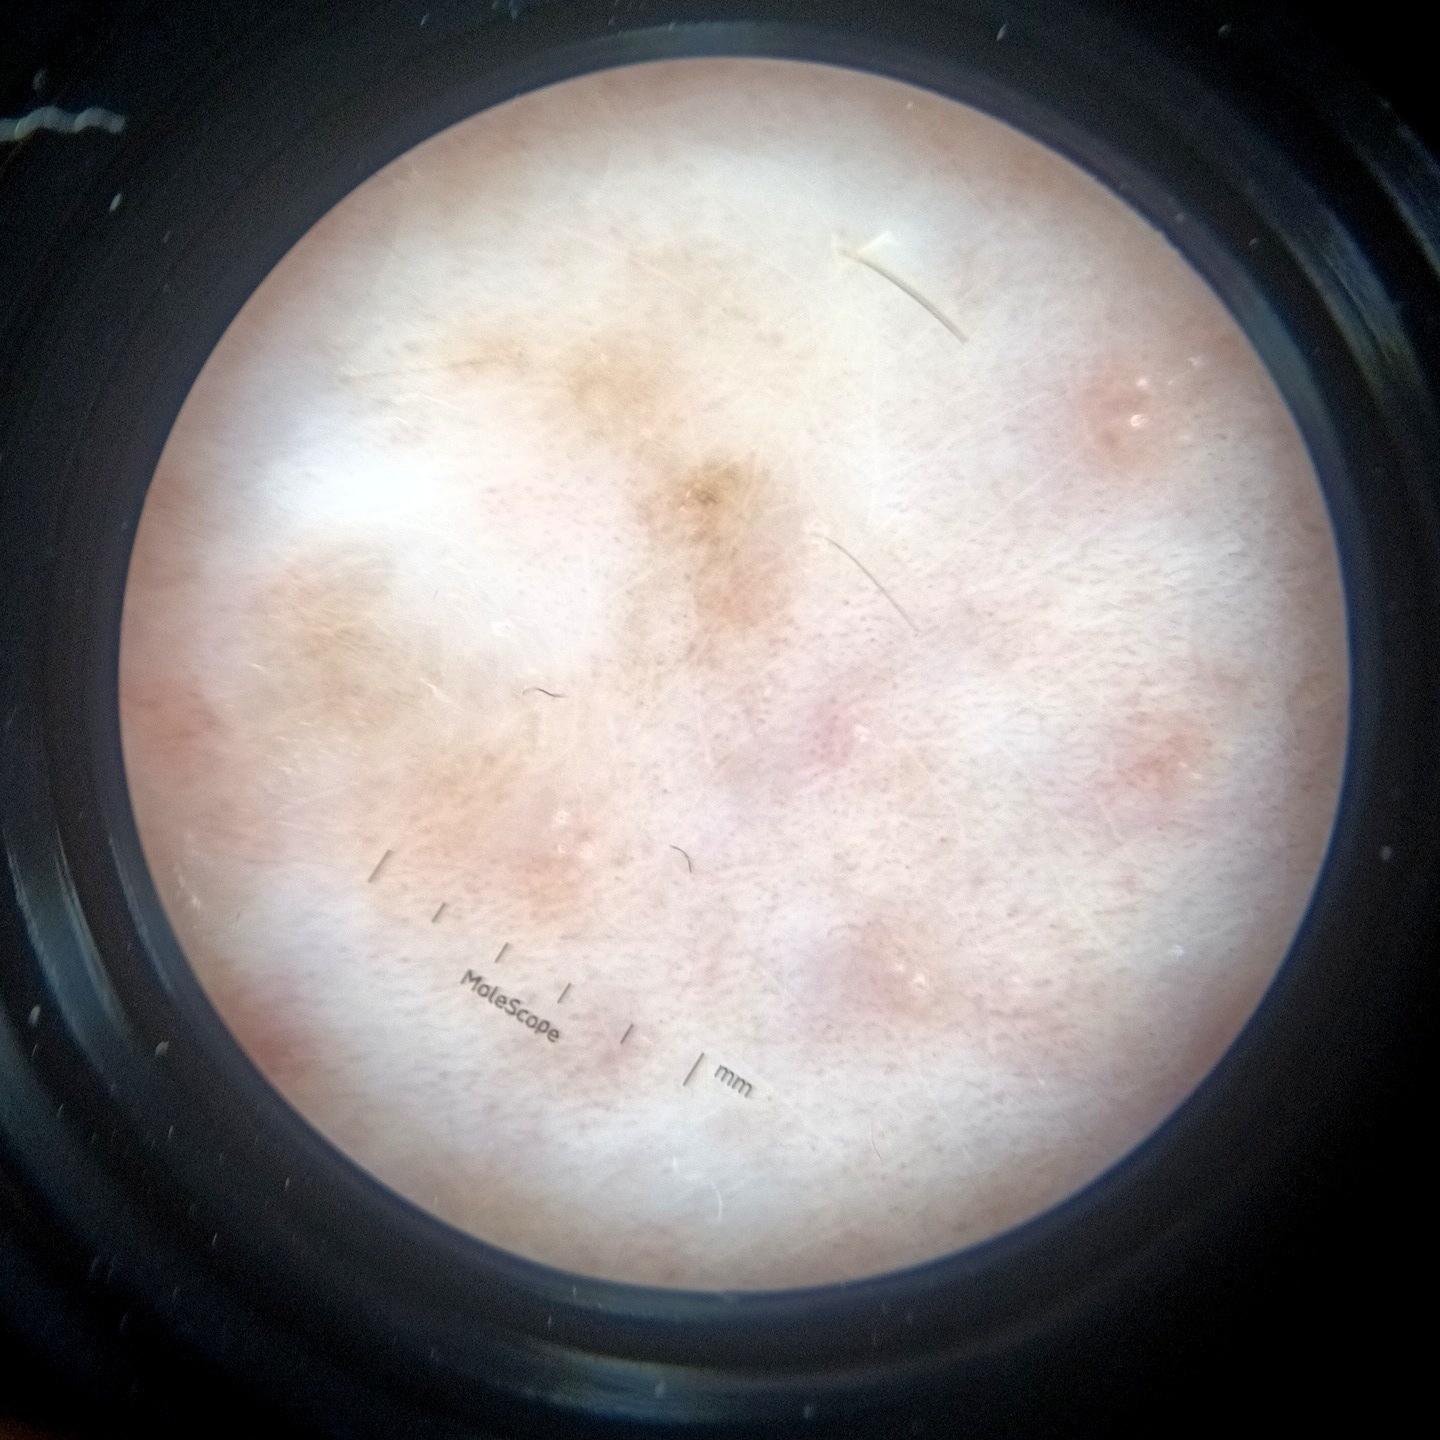

ISIC_3754278

acquisition_day 135

diagnosis_1 Benign

image_type dermoscopic